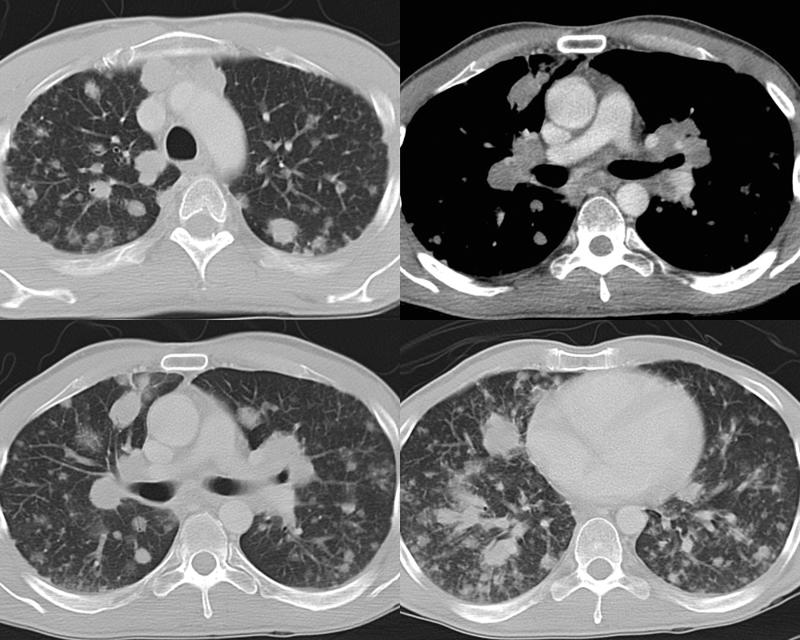

Gallery Mediastinum Lymphoma NHL

NHL